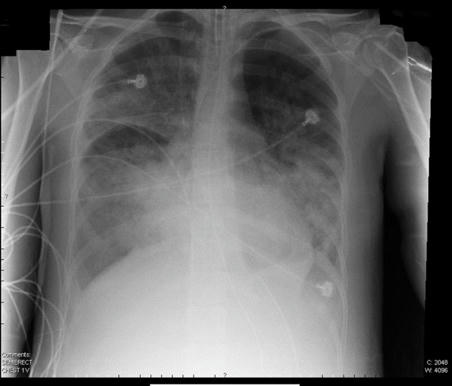

En Kingston, le diagnosticaron una infección vaginal que le había afectado los ovarios, por lo que procedieron a intervenirla quirúrgicamente para extirparlos. La indujeron en un coma, mientras los médicos informaron que la infección se había extendido a través del torrente sanguíneo afectando gravemente a sus pulmones por lo que empezó a padecer de un síndrome de dificultad respiratoria aguda (síndrome de distrés respiratorio agudo - SDRA). Anita necesitaba un respirador, pero el único existente en el hospital, ya se encontraba ocupado. “El lugar donde estaba internada era paupérrimo, una cama al lado de la otra. Tenía una infección en el abdomen que le llegó a los pulmones y casi la mata", contó a los medios Guillermo, el esposo.

Uno de los médicos que la atienden explicó que "El diagnóstico es crítico. Está grave. El pulmón está seriamente afectado, con una profunda inflamación que hace que se acumule líquido y que la oxigenación de la sangre no sea la óptima".

El parte médico agregaría que "Hubo una infección inicial que es pelviperitonitis que terminó comprometiendo el pulmón. Hay que completar la evaluación y decidir cambios en el tratamiento con antibióticos y con el soporte del respirador. Eso lo vamos a ir viendo en el momento a momento. El pulmón está seriamente infectado y también el abdomen donde fue sometida a una doble cirugía (en Jamaica)", y recordó que "La infección del pulmón provoca una inflamación del órgano que afecta la oxigenación de la sangre".